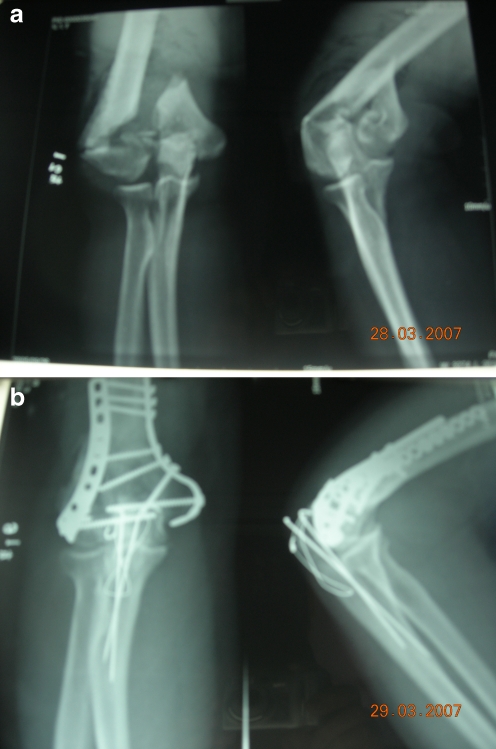

All operations were performed successfully with no intraoperative complications. A reconstructive plate (Trauson Medical Instrument Co., Ltd., Changzhou, China) was used in 21 cases and anatomical plate (Trauson Medical Instrument Co., Ltd.) in 35 cases (Fig. 1). External fixation was not performed in any case. Postoperative vacuum sealed drainage was used for patients with severe skin contusions.

Fig. 1.

Radiographs illustrating a representative type C distal humerus fracture. a Preoperative anteroposterior and lateral views. b Anteroposterior and lateral views following bilateral internal plate fixation via an olecranon osteotomy approach